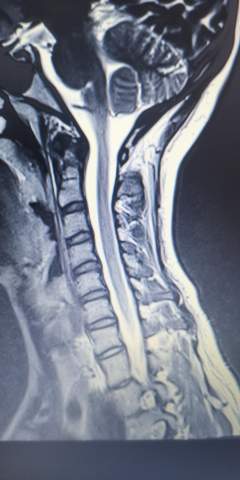

Mrt bilder hws bandscheibenvorfall. Bandscheibenvorfall der bis an. MRT-Bild und Beschwerdebild müssen. Ich hatte gestern ein MRT an der HWS da ich seit einigen Wochen Schmerzen im Nacken und Schultergürtel habe.

Jetzt meine neuen Ratgeber bestellen. Auf den MRT- CT-Schnittbildern werden die Größe und der genaue Ort des Vorfalls sichtbar. Die Wirbelkörper stehen zueinander regelrecht.

Auf dem MRT-Bild erkennt man dass die Bandscheibe noch immer mit der Hinterkante der Wirbelkörper abschließt und nicht in den dahinter liegenden Wirbelkanal eintritt was bei einem Bandscheibenvorfall der Fall wäre. Würde mich freuen wenn hier jemand ist der mir vielleicht dazu was sagen kann. Rückenmark Medulla spinalis Dornfortsatz.

Lesen Sie hier welche Kontrastmittel verwendet werden und welche Risiken das Kontrastmittel-MRT birgt MRT HWS - Auswertung und Bilder. Anschließend ist links ein MRT-Schnittbild einer Halswirbelsäule mit Kontrastmittel zu sehen welche einen Bandscheibenvorfall im HWS. Zur Abklärung wurde eine Kernspintomographie der Lendenwirbelsäule durchgeführt.

Herz Herz-Kreislauf-System zu stärken. Ersichtlich die Fehlstellung der HWS und die Bandscheibenvowölbungen.